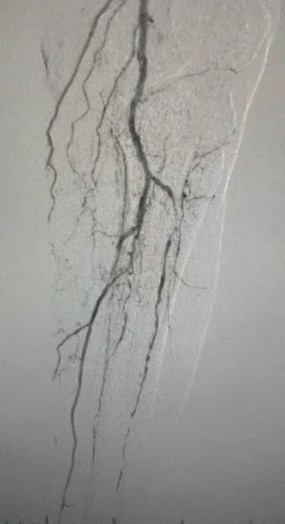

· Pencitraan preoperatif: menyebarkan stenosis parah, menyebarkan kalfikasi dalam jalan setapak anggota bawah bilateral

Prosedur pasca, stenosis arteri meningkat secara signifikan, aliran darah meningkat, dan suhu kulit mawar. Tidak ada terjadi komplikasi setelah operasi. Baik pasien maupun tim bedah sangat puas dengan hasilnya.